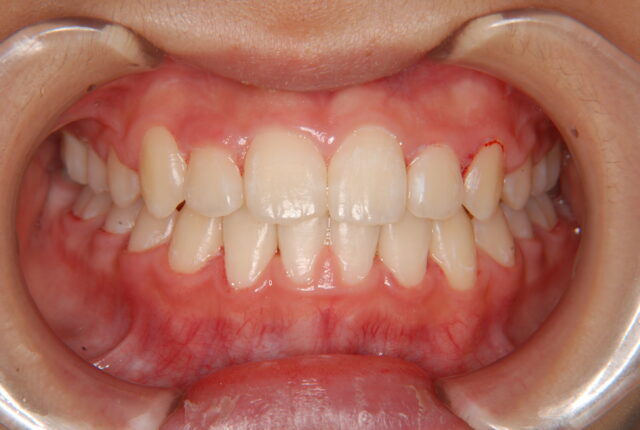

唇側矯正 小児矯正 反対咬合(受け口)の治療例【非抜歯】 この治療例は上下顎歯の唇側より矯正装置を装着して、反対咬合の改善を行った写真です。 治療前 治療後 主訴 受け口を治したい 診断名あるいは主な症状 下顎前突 年齢 10才 治療に用いた主な装置 唇側矯正装置 抜歯部位 非抜歯 治療期間 約2年 通院回数 24回 治療費概算 880,000円(税込) リスクと副作用 反対咬合を改善する時に上下の歯がぶつかり破折する可能性がある。下顎が後方に押し込まれ、顎関節に負担をかける可能性がある。